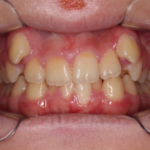

反対咬合(受け口)の症例

Before After 治療途中の小児矯正の症例です。 成長期に上顎の幅を広げ ...